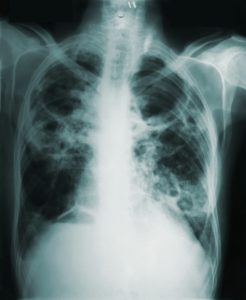

Røntgenundersøgelse

05 juli 2025